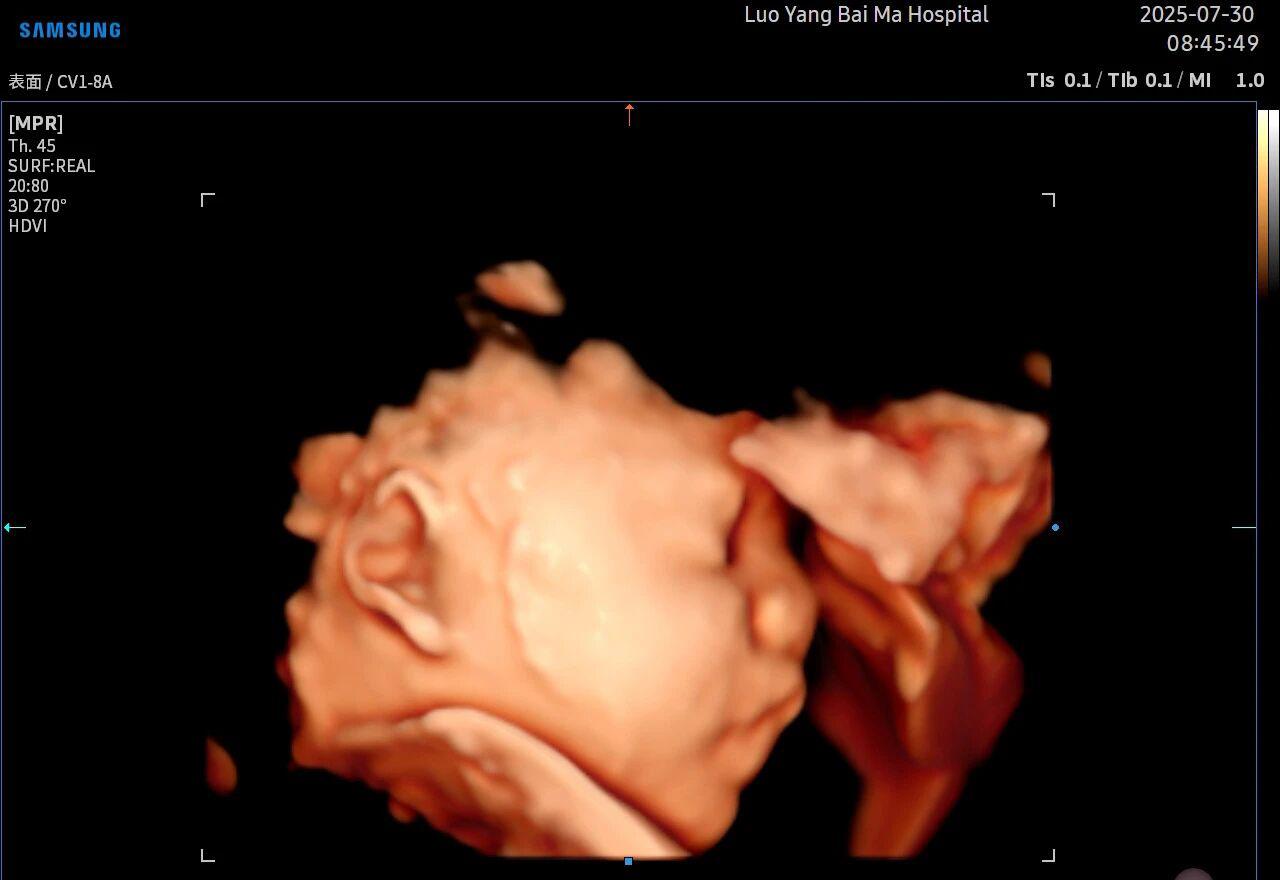

很多准妈妈可能对四维(4D)彩超已经非常熟悉,它能够实时动态地展示宝宝在宫内的活动,让我们看到宝宝打哈欠、伸懒腰的可爱模样,为无数家庭留下了珍贵的第一份“动态影集”。

4. 温情互动,一次充满感动的“亲子会面”

除了严谨的医学诊断价值,5D彩超也为准爸妈们带来了无与伦比的情感体验。通过高清逼真的动态影像,您可以清晰地看到宝宝的每一个细微表情和动作,仿佛他(她)就在眼前。这份提前到来的“亲密接触”,不仅能极大地缓解孕期的焦虑,更能加深家庭成员与未出世宝宝之间的情感连接,让等待的每一天都充满更具体的幸福感。